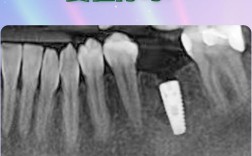

种牙前是否需要拍片,是许多准备接受种植牙手术的患者关心的问题,从临床实践来看,拍片不仅是必要的,更是保障种植牙成功和安全的关键环节,种植牙手术并非简单的“种螺丝”,而是需要通过精准的影像学检查,全面了解患者的口腔内部情况,从而制定个性化的治...